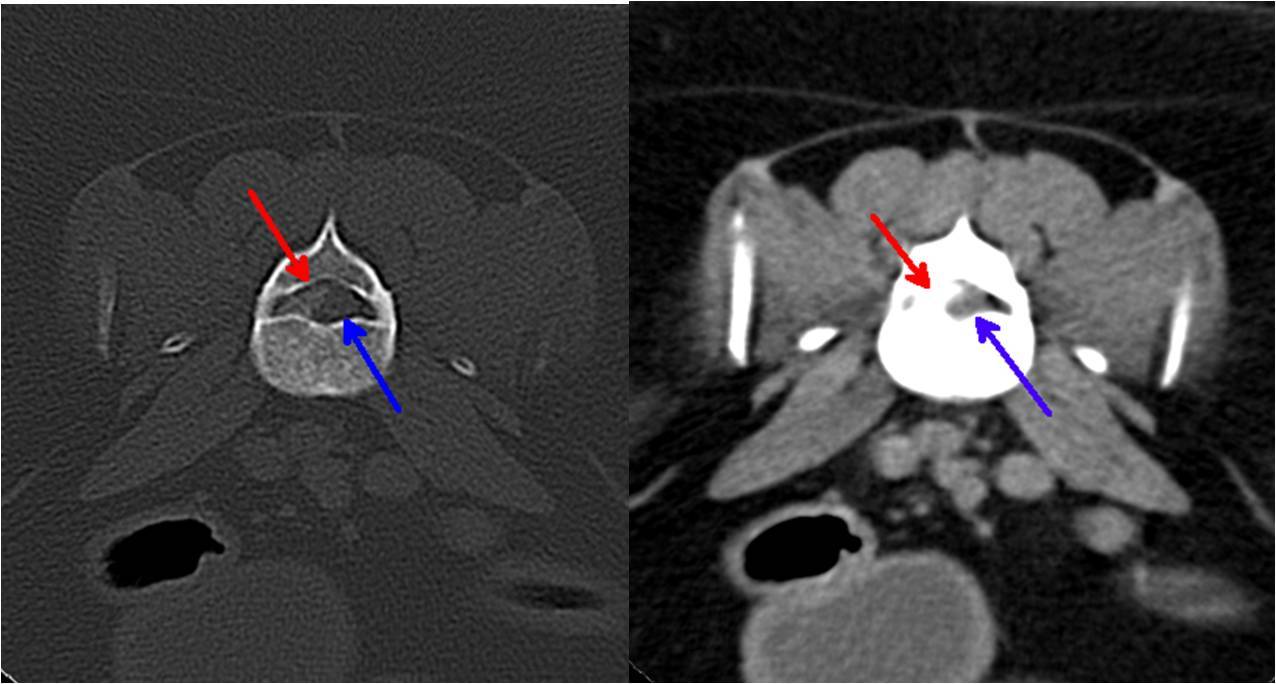

Die vor der Narkose durchgeführte Blutuntersuchung ergab keine Abweichungen von den Normalwerten. Die Röntgenbilder der Knie- und Hüftgelenke waren unauffällig. Bei der seitlichen Aufnahme der Lendenwirbelsäule fiel ein verengter und unruhiger Zwischenwirbelspalt zwischen dem 6. und 7. Lendenwirbel auf (Bild 1). Es wurde der Verdacht auf eine Bandscheibenerkrankung in diesem Bereich geäußert und den Besitzern eine weitere Abklärung mittels Computertomographie empfohlen. In der computertomographischen Untersuchung der Wirbelsäule konnte zwischen dem 6. und 7. Lendenwirbel in den knöchernen Wirbelkanal sowie in das linke Nervenaustrittsloch vorgefallenes Bandscheibenmaterial nachgewiesen werden (Bild 2 und 3). Dieses verursachte eine Kompression des Nervengewebes. Dieser Druck des vorgefallenen Bandscheibenmaterials auf das Nervengewebe war ursächlich für die hochgradige Schmerzhaftigkeit.